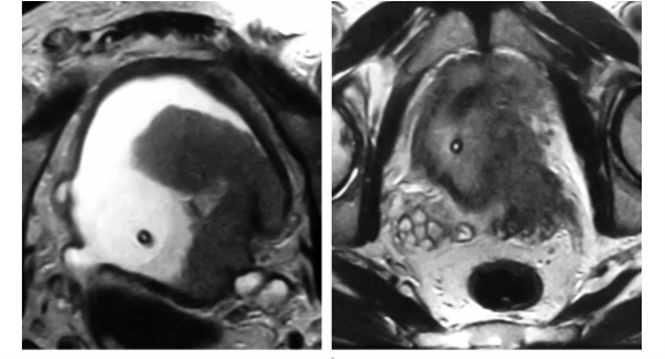

50F

Mixed epithelial and stromal tumor (MEST)